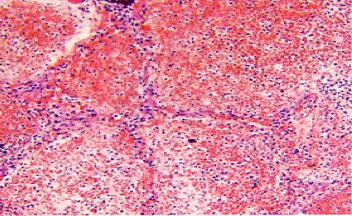

大叶性肺炎其病变主要为肺泡内的纤维素性渗出性炎症。一般只累及单侧肺,以下叶多见,也可先后或同时发生于两个以上肺叶,如图1-1。

(图1-1,病变弥漫性—大叶性肺炎)